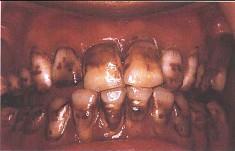

问题 关于氟斑牙,下列哪个说法是错误 ( )

选项 A.氟主要损害釉质发育期牙胚的造釉细胞 B.饮用水是摄入氟的最大来源 C.深层釉质含氟量是表面釉质的11倍左右 D.又称斑釉牙 E.慢性氟中毒患者可有骨骼增殖性变化

答案 C